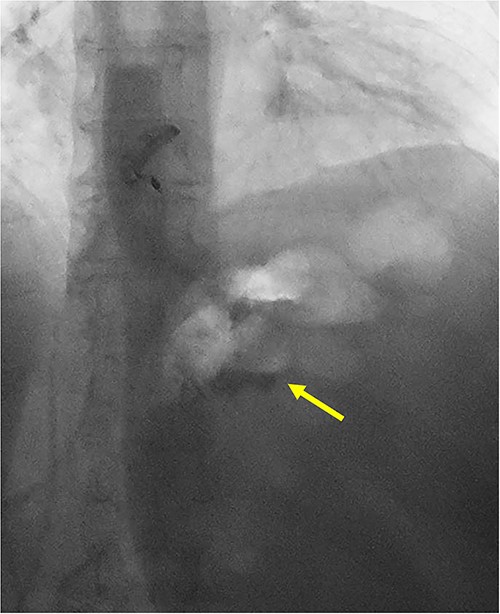

She underwent a CT of her abdomen and pelvis that showed concern for a possible gastrogastric fistula (Fig. 1) that was confirmed via an upper GI series demonstrating the passage of oral contrast into the remnant stomach (Fig. 2). Subsequent esophagogastroduodenoscopy (EGD) also revealed an ulcer at the site of the GGF (Fig. 3). The patient was discharged home on Omeprazole twice daily. She was seen in the outpatient setting with bariatric surgery and scheduled in 3 months for laparoscopic take-down of her gastrogastric fistula.

UGI series demonstrating passage of oral contrast from gastric pouch to remnant stomach.

Pre-operative EGD demonstrating wide-mouthed gastrogastric fistula with an associated ulcer.